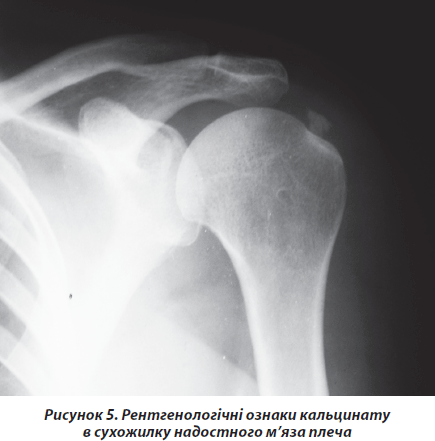

Третю групу хворих становили 152 пацієнта зі скаргами на біль в еполетній зоні плеча з іррадіацією до верхньої третини передпліччя. У 132 хворих біль мав характер хронічного, постійного, ниючого, гризучого, що посилювався при відведенні плеча в межах 70–120°. Захворювання у них розвивалось поступово протягом декількох місяців або років. Точніші дані навести неможливо через те, що пацієнти не могли уточнити дату початку захворювання, що ще раз свідчить про його поступовий розвиток. Проте у 20 пацієнтів захворювання розпочалось із різкого болю вказаної локалізації, що мав характер сіпаючого, прострільного, больовий синдром різко обмежував рухи в кінцівці. У хворих були позитивні тести Hаwkins, імпінджмент-тест (рис. 1). На рентгенограмах відмічались вогнища затемнення в проекції місця прикріплення сухожилка надостного м’яза без контакту з великим горбком (рис. 5).

Під час ультразвукового дослідження плеча у хворих відмічалось гіперехогенне вогнище, локалізоване в товщі сухожилка надостного мяза. Таким хворим ми встановлювали діагноз кальціфікуючого тендиніту сухожилка надостного м’яза. Відомо, що в ділянці прикріплення сухожилка надостного м’яза до плечової кістки існує зона критичного кровообігу. Саме в цьому місці найчастіше винкає некроз сухожилка з подальшим заміщенням некротизованого сухожилка пірофосфатом кальцію [10]. При локалізації кальцінату в товщі сухожилка надостного м’яза виникають симптоми субакроміального конфлікту, виявлені в більшості хворих. Проте при пошкодженні покривного шару сухожилка виникає вихід речовини кальцинату в порожнину субакроміальної сумки [10]. Пірофосфат кальцію є осмотично активним, викликає різкий біль та запалення в субакроміальній сумці, чим пояснюються клінічні прояви в меншої кількості пацієнтів даної групи. Лікування хворих даної групи ми проводили двома методиками. Перша методика заснована на тому, що кальцинат не є петрифікатом, фактично це депо кристалів колоїдної речовини, що не розчиняється у воді, проте може бути механічно вимита. За допомогою ультразвукового апарату виявляли кальцинат, після місцевого знеболення поверхневого шару тканин розчином місцевого анестетика, під ультразвуковим контролем у кальцинат вводили голку для спинномозкової анестезії 16 G. До голки під’єднували шприц, наповнений фізіологічним розчином. Під час циклів послідовного нагнітання — аспірації фізіологічного розчину вимивали кальцинат (рис. 6).